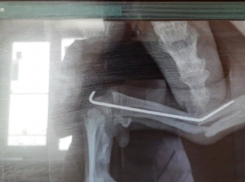

Общество «Врач пытался сохранить кость»: в клинике Волжского прокомментировали историю с ампутацией лапы шпицу

Лапку пришлось ампутировать